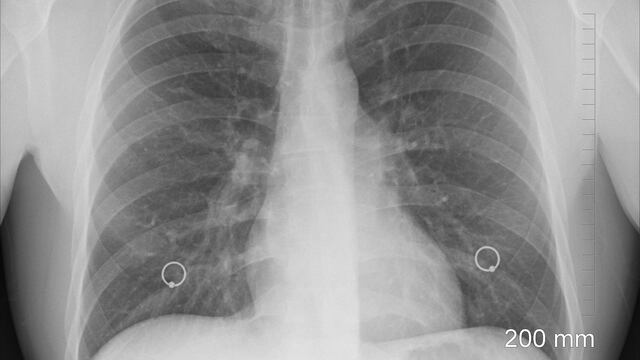

Asimismo, el equipo de Gholamrezanezhad registró al menos 919 imágenes de TAC en pacientes de estudios previos publicados y encontraron que los lóbulos inferiores de los pulmones son los que se dañan con mayor frecuencia.

Es decir que las imágenes estaban llenas de parches opacos en los pulmones que indican inflamación, esto puede dificultar la respiración y, aunque este daño puede disminuir con el tiempo, un estudio austraco encontró que el 88% de los participantes presentaban el daño pulmonar 6 semanas después de haber superado el coronavirus.